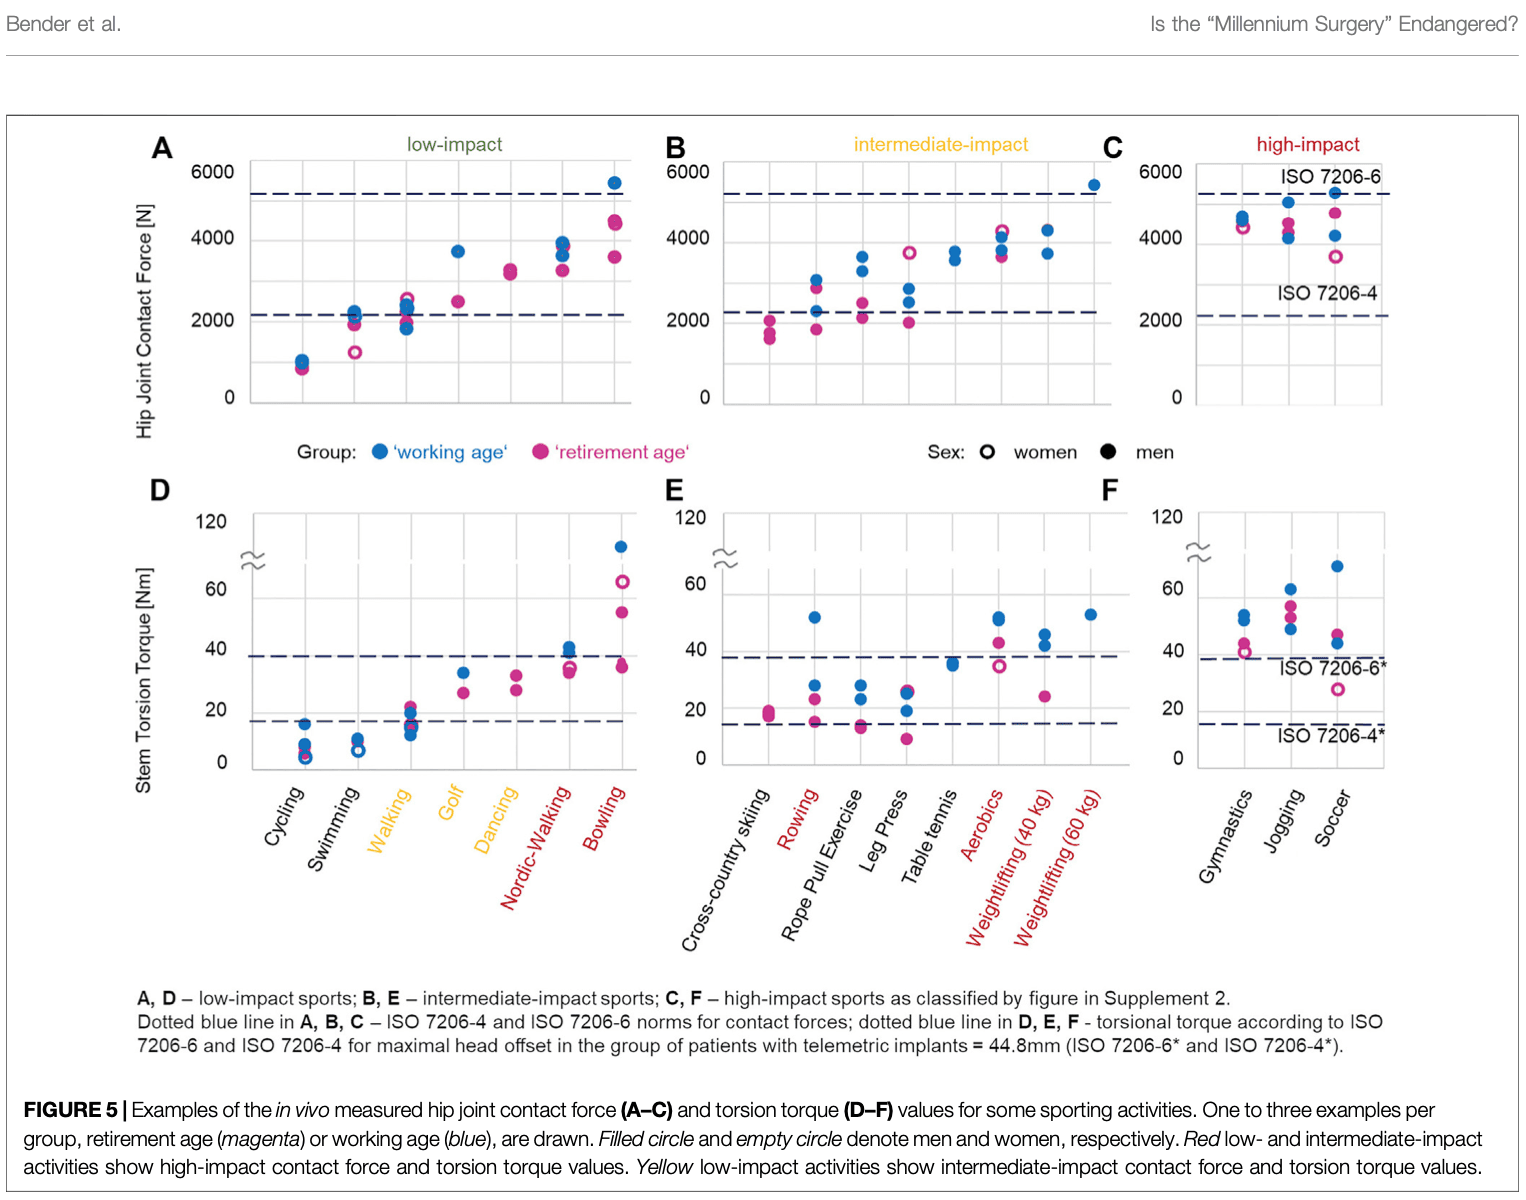

这个汇总表有话要说。 2022 年,本德测量了活体关节接触力和扭转力矩,发现保龄球等被认为是低冲击力的活动,与高冲击力的足球相比,会产生更高的关节接触力和扭转力矩。 此外,他们还发现体重和体重指数也会影响日常活动中的这些力。